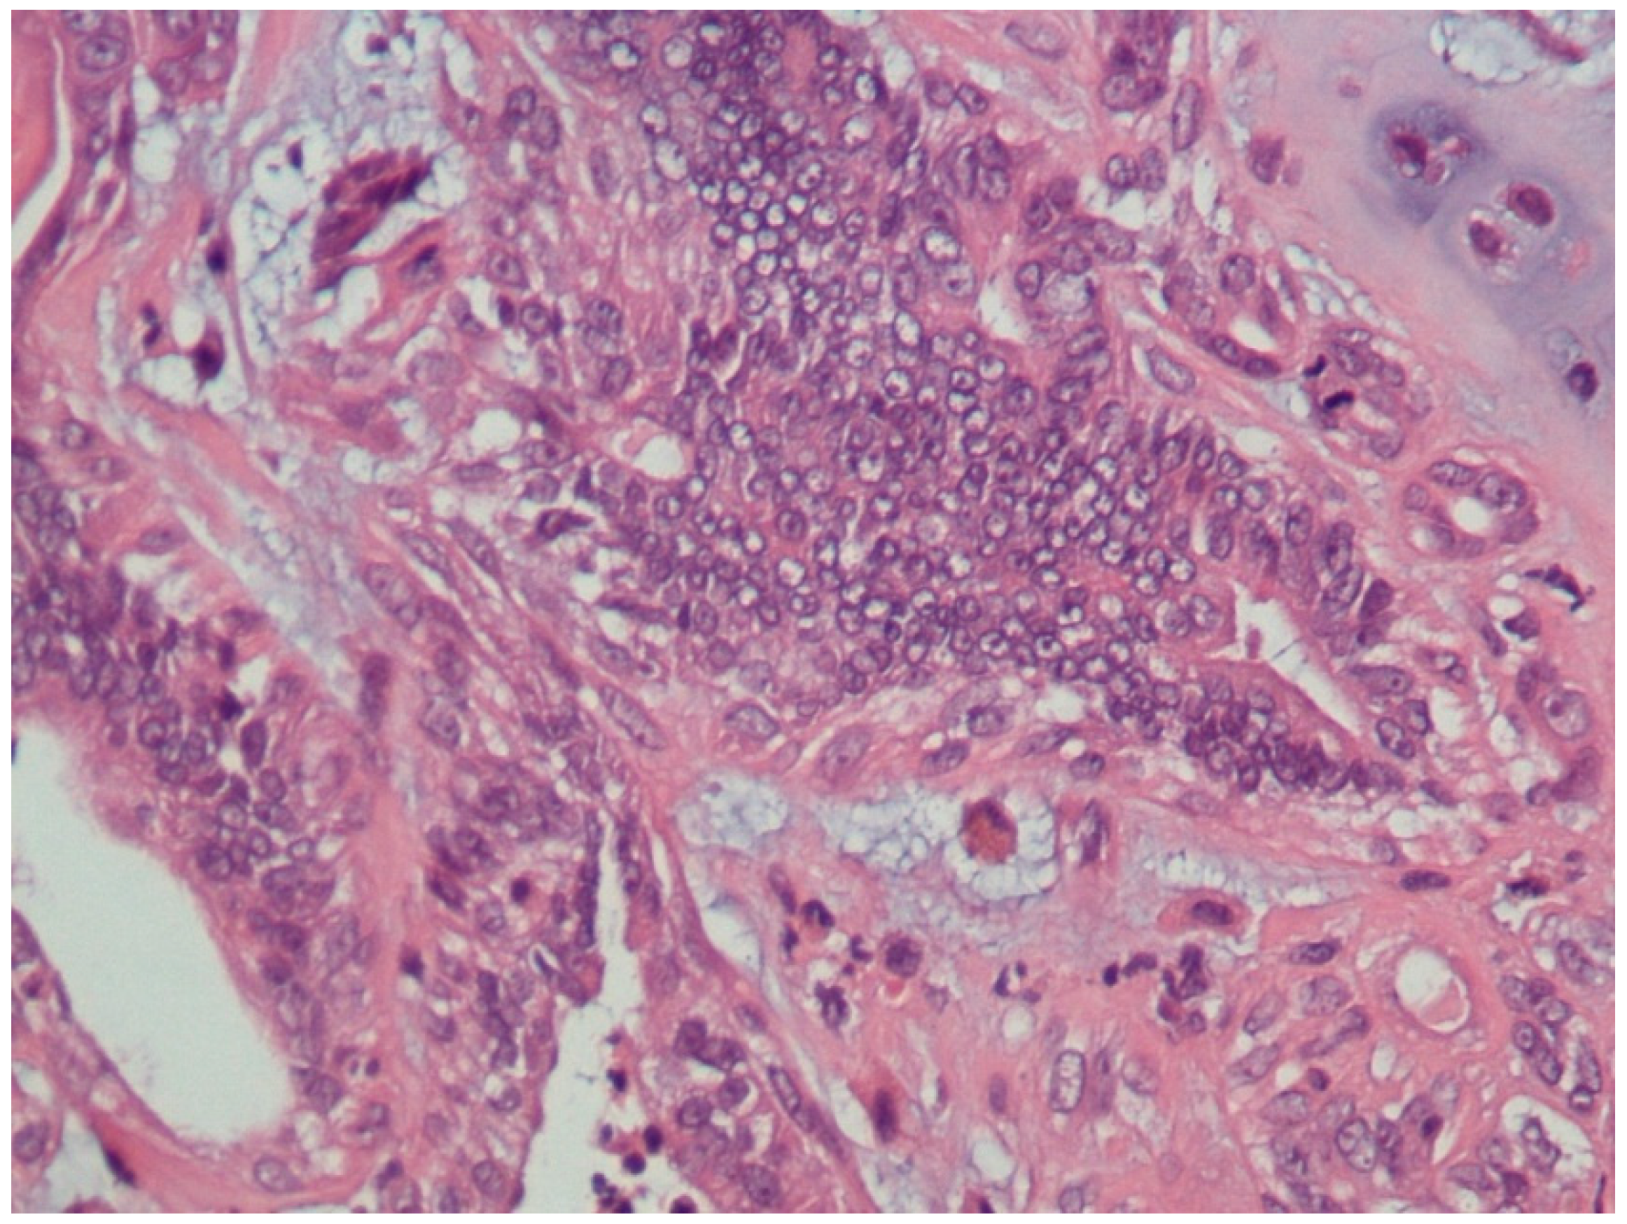

3.1. Histopathological Assessment